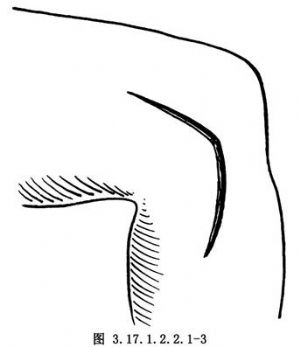

外側正中弧形切口。自髕上2cm開始,在關節線向後彎曲,離開髕骨、髕腱3cm,至腓骨小頭下3cm(圖3.17.1.2.2.1-3)。